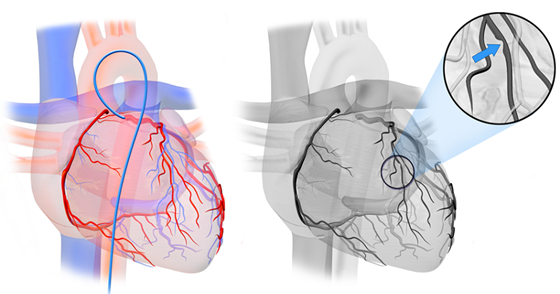

今年2月底,刘阿姨来到湘雅常德医院心内科,范爱德副主任医师仔细询问病史后,结合患者各种检查认为还是要考虑冠心病 心绞痛可能,建议刘阿姨住院,进一步完善冠脉造影明确冠心病。2月27日,据刘阿姨的冠脉造影显示,她的三条动脉都有不同程度的狭窄,其中一条动脉(左前降支)重度狭窄并钙化。心内科为刘阿姨做了冠脉介入治疗手术,于前降支近段及中段狭窄处植共植入2枚支架后,狭窄的血管顺利开通,心肌得到供血。历时近一年的求医之路,今天终于看到曙光,刘阿姨放心了……

支架植入术前

支架植入术后